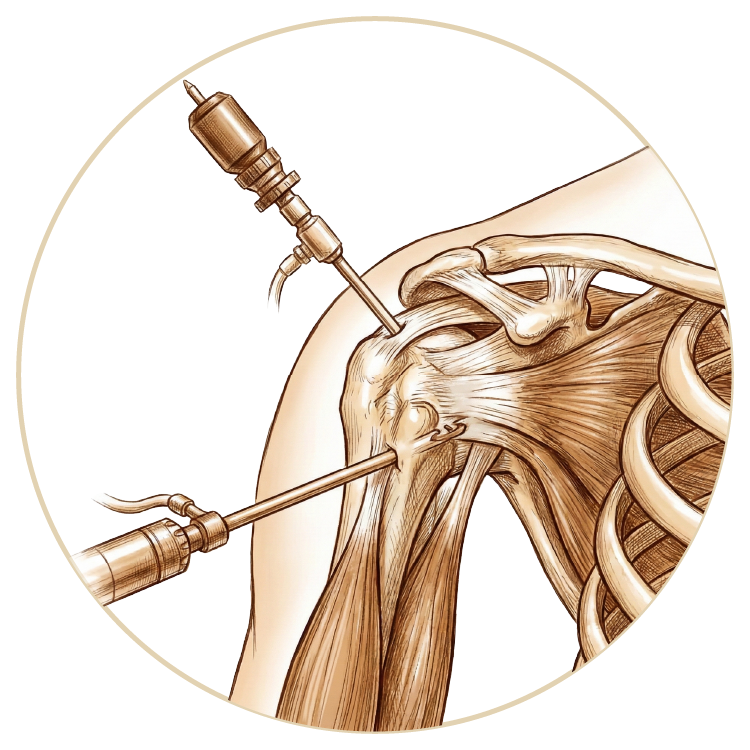

Omuz Hastalıkları ve Tedavileri

Omuz Çıkığı

Omuz Hastalıkları

Rotator Manşet Yaralanmaları

Omuz Artroskopisi